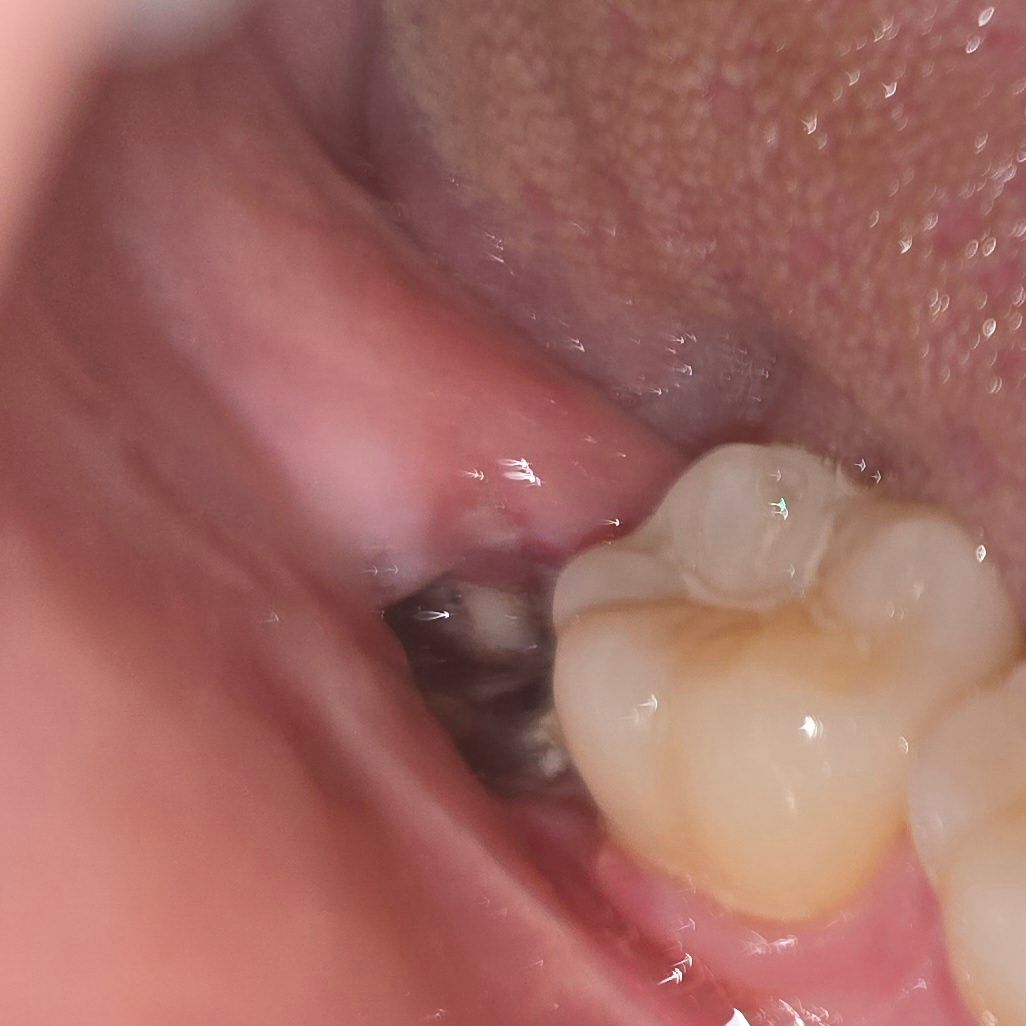

매복사랑니 발치 4일차) 드라이소켓 가능성 있을까요..? (발치부위 사진 주의)

안녕하세요, 발치한지 4일차(어제)에 고여있던 피떡이 사라지더니 5일차(오늘)부터 저런 하얀부분들이 군데군데 보이기 시작하더라고요...

발치 첫날부터 지금까지 통증도 거의 없었고...지금도 드문드문 비릿한 맛이 나는거 외엔 특이사항은 없는데.... 구멍이 뚫린 뒤로 너무 불안하더라고요...ㅜㅜ 침을 너무 세게 삼켜서 그런거아닌지 싶기도 하고...ㅠ치과 방문하려면 주말까지 기다려야돼서 도움받을 수 있을까하여 질문 드립니다ㅠㅠ

• 1번 째 사진

지금 사진에 보이는 것으로는 드라이소켓으로 보이지는 않습니다. 크게 문제는 없어보입니다

치유 과정 중에 나타나는 염증, 육아조직 반응으로 보입니다. 특별히 치유부전이나 드라이소켓의 양상은 아닙니다. 더군다나 통증이 심하지 않다면 괜찮습니다.